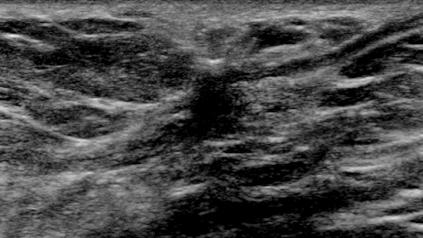

The target dataset was developed from 35 breast ultrasound scans that were segmented by an image-processing expert with extensive experience in breast lesion segmentation (the second author). The images, collected from the Web, are of different dimensions, ranging from to pixels (Figure 3, images resized for sake of illustration). These are the same images used to introduce EFIS originally [1].

Ultrasound images are generally difficult to segment, primarily due to the presence of speckle noise and low level of local contrast. It should be noted that the segmentation of ultrasound actually does require a complete processing chain, (including proper preprocessing and post-processing steps). However, the purpose of using these images was solely to demonstrate that the accuracy of the segmentation can be increased with the application of SC-EFIS.